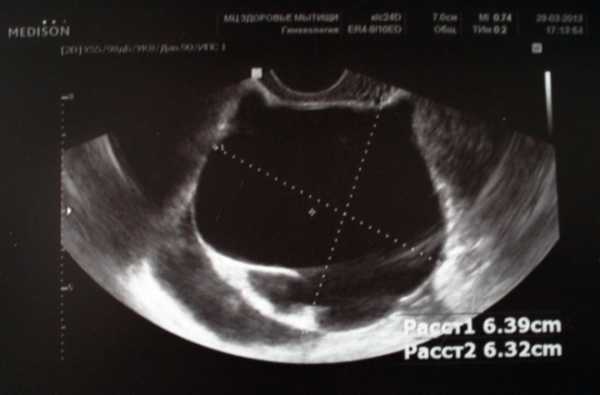

Π ΡΠ»ΡΡΠ°Π΅, Π΅ΡΠ»ΠΈ ΠΎΠ±ΡΠ°Π·ΠΎΠ²Π°Π½ΠΈΠ΅ Π΄ΠΎΡΡΠΈΠ³Π°Π΅Ρ ΡΠ°Π·ΠΌΠ΅ΡΠΎΠ² ΠΎΡ 6 Π΄ΠΎ 10 ΡΠ°Π½ΡΠΈΠΌΠ΅ΡΡΠΎΠ², Π½Π°Π±Π»ΡΠ΄Π°ΡΡΡΡ ΡΠ°Π·Π½ΠΎΠΎΠ±ΡΠ°Π·Π½ΡΠ΅ ΡΠΈΠΌΠΏΡΠΎΠΌΡ. ΠΠ΅ΡΡΡΠ½ΡΠ΅ ΠΈΠ΄ΡΡ Π΄ΠΎΠ»Π³ΠΎ ΠΈ ΠΎΠ±ΠΈΠ»ΡΠ½ΠΎ. ΠΠΎΡΠ»Π΅ ΡΠ΅ΠΊΡΠ° Π½Π°Π±Π»ΡΠ΄Π°ΡΡΡΡ Π²ΡΠ΄Π΅Π»Π΅Π½ΠΈΡ ΠΊΡΠ°ΡΠ½ΠΎΠ³ΠΎ ΡΠ²Π΅ΡΠ°. ΠΠ΅Π½ΡΡΡΡΠ°Π»ΡΠ½ΡΠΉ ΡΠΈΠΊΠ» Π½Π°ΡΡΡΠ°Π΅ΡΡΡ, ΠΌΠ΅ΡΡΡΠ½ΡΠ΅ ΠΏΡΠΎΡ ΠΎΠ΄ΡΡ ΠΎΡΠ΅Π½Ρ Π±ΠΎΠ»Π΅Π·Π½Π΅Π½Π½ΠΎ. ΠΡΡΡΠ°ΡΡΡΡ Π±ΠΎΠ»ΠΈ Π² ΠΆΠΈΠ²ΠΎΡΠ΅, Π²ΠΎΠ·Π½ΠΈΠΊΠ°Π΅Ρ ΡΡΠ²ΡΡΠ²ΠΎ, ΡΡΠΎ Π΅Π³ΠΎ ΡΠ°ΡΠΏΠΈΡΠ°Π΅Ρ. ΠΠΎΠ²ΡΡΠ°Π΅ΡΡΡ ΡΠ΅ΠΌΠΏΠ΅ΡΠ°ΡΡΡΠ° ΡΠ΅Π»Π°. ΠΠΎΡΡΠ½Π°Ρ ΠΎΠΏΡΡ ΠΎΠ»Ρ ΡΠ°ΠΊΠΎΠ³ΠΎ Π²ΠΈΠ΄Π° ΠΌΠΎΠΆΠ΅Ρ Π²ΠΎΠ·Π½ΠΈΠΊΠ½ΡΡΡ ΠΊΠ°ΠΊ Π½Π° ΠΏΡΠ°Π²ΠΎΠΌ, ΡΠ°ΠΊ ΠΈ Π½Π° Π»Π΅Π²ΠΎΠΌ ΡΠΈΡΠ½ΠΈΠΊΠ΅.

ΠΡΠ»ΠΈ Π²ΡΠ°Ρ Π·Π°ΠΌΠ΅ΡΠ°Π΅Ρ ΠΏΡΠΈΠ·Π½Π°ΠΊΠΈ ΠΊΠΈΡΡΡ ΡΠΈΡΠ½ΠΈΠΊΠ° Ρ ΠΆΠ΅Π½ΡΠΈΠ½Ρ, ΠΎΠ½ Π½Π°Π·Π½Π°ΡΠ°Π΅Ρ ΠΏΠΎΠ»Π½ΠΎΠ΅ ΠΎΠ±ΡΠ»Π΅Π΄ΠΎΠ²Π°Π½ΠΈΠ΅ ΠΎΡΠ³Π°Π½ΠΈΠ·ΠΌΠ° ΠΈ ΡΠΌΠΎΡΡΠΈΡ ΠΊΠ°ΠΊ Π²ΡΠ³Π»ΡΠ΄ΠΈΡ ΠΊΠΈΡΡΠ° ΡΠΈΡΠ½ΠΈΠΊΠ° Π½Π° Π£ΠΠ. ΠΠΎΡΠ»Π΅Π΄Π½Π΅Π΅ ΠΈΡΡΠ»Π΅Π΄ΠΎΠ²Π°Π½ΠΈΠ΅ ΠΏΠΎΠ·Π²ΠΎΠ»ΡΠ΅Ρ ΠΎΠΏΡΠ΅Π΄Π΅Π»ΠΈΡΡ Π½Π΅ ΠΏΡΠΎΠΈΠ·ΠΎΡΠ»ΠΎ Π»ΠΈ ΠΏΠ΅ΡΠ΅ΠΊΡΡΡΠΈΠ²Π°Π½ΠΈΠ΅ Π½ΠΎΠΆΠΊΠΈ Π½ΠΎΠ²ΠΎΠΎΠ±ΡΠ°Π·ΠΎΠ²Π°Π½ΠΈΡ ΠΈ Π½Π΅ Π³ΡΠΎΠ·ΠΈΡ Π»ΠΈ ΠΏΠ°ΡΠΈΠ΅Π½ΡΠΊΠ΅ ΡΠ°Π·ΡΡΠ² Π½ΠΎΠ²ΠΎΠΎΠ±ΡΠ°Π·ΠΎΠ²Π°Π½ΠΈΡ, ΠΊΡΠΎΠΌΠ΅ ΡΠΎΠ³ΠΎ Π£ΠΠ ΠΏΠΎΠ·Π²ΠΎΠ»ΡΠ΅Ρ ΠΎΠΏΡΠ΅Π΄Π΅Π»ΠΈΡΡ ΡΠ°Π·ΠΌΠ΅Ρ Π½ΠΎΠ²ΠΎΠΎΠ±ΡΠ°Π·ΠΎΠ²Π°Π½ΠΈΡ. ΠΠΎΡΠΏΠ°Π»Π΅Π½ΠΈΠ΅ ΠΊΠΈΡΡΡ Π½Π΅ Π²ΡΠ΅Π³Π΄Π° Π³ΡΠΎΠ·ΠΈΡ ΠΎΠΏΠ΅ΡΠ°ΡΠΈΠ΅ΠΉ, Π½ΠΎ Π΅ΡΠ»ΠΈ Π² ΠΊΡΠ°ΡΡΠ°ΠΉΡΠΈΠ΅ ΡΡΠΎΠΊΠΈ ΠΏΠΎΡΠ»Π΅ Π½Π°ΡΠ°Π»Π° Π»Π΅ΡΠ΅Π½ΠΈΡ ΡΠ»ΡΡΡΠ΅Π½ΠΈΠ΅ Π½Π΅ Π½Π°ΡΡΡΠΏΠ°Π΅Ρ, ΡΠΎ Π²ΡΠ°Ρ ΠΌΠΎΠΆΠ΅Ρ ΡΠ°ΡΡΠΌΠ°ΡΡΠΈΠ²Π°ΡΡ ΠΊΠ°ΠΊ Π²Π°ΡΠΈΠ°Π½Ρ Ρ ΠΈΡΡΡΠ³ΠΈΡΠ΅ΡΠΊΠΎΠ΅ Π²ΠΌΠ΅ΡΠ°ΡΠ΅Π»ΡΡΡΠ²ΠΎ.

ΠΠ½ΠΎΠ³ΠΈΠ΅ ΠΊΠΈΡΡΡ ΡΠΈΡΠ½ΠΈΠΊΠΎΠ², ΠΈΠΌΠ΅ΡΡΠΈΠ΅ ΡΠ°Π·ΠΌΠ΅Ρ Π±ΠΎΠ»ΡΡΠ΅ ΡΠ΅ΡΡΡΠ΅Ρ ΡΠ°Π½ΡΠΈΠΌΠ΅ΡΡΠΎΠ² ΠΈ Π½Π΅ ΡΠ°ΡΡΠ°ΡΡΠ²Π°ΡΡΠΈΠ΅ΡΡ Π² ΡΠ΅ΡΠ΅Π½ΠΈΠ΅ Π΄Π²ΡΡ -ΡΡΠ΅Ρ ΠΌΠ΅Π½ΡΡΡΡΠ°Π»ΡΠ½ΡΡ ΡΠΈΠΊΠ»ΠΎΠ², ΡΠ°ΠΊΡΠΈΡΠ΅ΡΠΊΠΈ ΡΠ²Π»ΡΡΡΡΡ ΡΡΠ½ΠΊΡΠΈΠΎΠ½Π°Π»ΡΠ½ΡΠΌΠΈ. Π’Π°ΠΊΠΈΠ΅ ΠΊΠΈΡΡΡ ΡΠΎΡΠΌΠΈΡΡΡΡΡΡ, ΠΊΠΎΠ³Π΄Π° ΡΠΎΠ»Π»ΠΈΠΊΡΠ», ΡΠΈΠ·ΠΈΠΎΠ»ΠΎΠ³ΠΈΡΠ΅ΡΠΊΠ°Ρ ΠΊΠΈΡΡΠ°, Π²Π½ΡΡΡΠΈ ΠΊΠΎΡΠΎΡΠΎΠΉ ΡΠΎΠ·ΡΠ΅Π²Π°Π΅Ρ ΡΠΉΡΠ΅ΠΊΠ»Π΅ΡΠΊΠ°, ΠΏΠΎ ΠΊΠ°ΠΊΠΈΠΌ-ΡΠΎ ΠΏΡΠΈΡΠΈΠ½Π°ΠΌ Π½Π΅ ΡΠ°ΡΡΠ΅Ρ, Π° ΡΠ»Π΅Π΄ΠΎΠ²Π°ΡΠ΅Π»ΡΠ½ΠΎ, Π½Π΅ Π²ΡΡΠ²ΠΎΠ±ΠΎΠΆΠ΄Π°Π΅Ρ ΡΠΉΡΠ΅ΠΊΠ»Π΅ΡΠΊΡ Π½ΠΎΡΠΌΠ°Π»ΡΠ½ΡΠΌ ΠΏΡΡΠ΅ΠΌ. ΠΠΎΠ³Π΄Π° ΡΡΠΎ ΠΏΡΠΎΠΈΡΡ ΠΎΠ΄ΠΈΡ, ΡΠΎΠ»Π»ΠΈΠΊΡΠ» Π½Π° ΡΠΈΡΠ½ΠΈΠΊΠ΅ ΠΌΠΎΠΆΠ΅Ρ ΠΏΡΠΎΠ΄ΠΎΠ»ΠΆΠ°ΡΡ ΡΠ°ΡΡΠΈ ΠΈ ΠΏΠΎΡΠ»Π΅ ΡΠΎΠ³ΠΎ ΠΌΠΎΠΌΠ΅Π½ΡΠ°, ΠΊΠΎΠ³Π΄Π° Π΄ΠΎΠ»ΠΆΠ½Π° Π±ΡΠ»Π° Π±Ρ ΠΏΡΠΎΠΈΠ·ΠΎΠΉΡΠΈ ΠΎΠ²ΡΠ»ΡΡΠΈΡ. ΠΠ½ΠΎΠ³Π΄Π° ΠΎΠ½ Π΄ΠΎΡΡΠΈΠ³Π°Π΅Ρ ΡΠ°Π·ΠΌΠ΅ΡΠ° ΡΠ΅ΠΌΡ-Π²ΠΎΡΠ΅ΠΌΡ ΡΠ°Π½ΡΠΈΠΌΠ΅ΡΡΠΎΠ² Π² Π΄ΠΈΠ°ΠΌΠ΅ΡΡΠ΅ ΠΈ ΠΌΠΎΠΆΠ΅Ρ Π²ΡΠ·ΡΠ²Π°ΡΡ Π±ΠΎΠ»ΠΈ. Π Π°Π½Π°ΠΌΠ½Π΅Π·Π΅, ΠΊΠΎΡΠΎΡΡΠΉ ΡΡΠ°Π²ΠΈΡΡΡ ΠΏΠΎ ΡΠ΅Π·ΡΠ»ΡΡΠ°ΡΠ°ΠΌ ΡΠ»ΡΡΡΠ°Π·Π²ΡΠΊΠΎΠ²ΠΎΠ³ΠΎ ΠΈΡΡΠ»Π΅Π΄ΠΎΠ²Π°Π½ΠΈΡ, ΠΊΠΈΡΡΡ ΡΡΠΎΠ³ΠΎ ΡΠΈΠΏΠ° ΠΎΠΏΠΈΡΡΠ²Π°ΡΡΡΡ ΠΊΠ°ΠΊ ΠΎΠ΄Π½ΠΎΠΏΠΎΠ»ΠΎΡΡΠ½ΡΠ΅ ΠΈ ΡΠΎΠ½ΠΊΠΎΡΡΠ΅Π½Π½ΡΠ΅. ΠΠΌΠ΅Π΅ΡΡΡ Π² Π²ΠΈΠ΄Ρ, ΡΡΠΎ ΠΎΠ½ΠΈ ΡΠΎΡΡΠΎΡΡ ΠΈΠ· ΠΎΠ΄Π½ΠΎΡΠΎΠ΄Π½ΠΎΠΉ ΠΆΠΈΠ΄ΠΊΠΎΡΡΠΈ, ΠΎΠΊΡΡΠΆΠ΅Π½Π½ΠΎΠΉ ΡΠΎΠ½ΠΊΠΎΠΉ ΠΎΠ±ΠΎΠ»ΠΎΡΠΊΠΎΠΉ. ΠΠ±ΡΡΠ½ΠΎ ΠΎΠ½ΠΈ ΡΠ°ΡΡΠ°ΡΡΠ²Π°ΡΡΡΡ ΡΠ°ΠΌΠΈ ΠΏΠΎ ΡΠ΅Π±Π΅, Π½ΠΎ ΠΈΠ½ΠΎΠ³Π΄Π° ΠΏΡΠΎΠ΄ΠΎΠ»ΠΆΠ°ΡΡ ΡΠ°ΡΡΠΈ ΠΈ ΡΡΠ΅Π±ΡΡΡ Ρ ΠΈΡΡΡΠ³ΠΈΡΠ΅ΡΠΊΠΎΠ³ΠΎ Π²ΠΌΠ΅ΡΠ°ΡΠ΅Π»ΡΡΡΠ²Π°. Π₯ΠΎΡΡ Π½Π΅ΠΊΠΎΡΠΎΡΡΠ΅ Π²ΡΠ°ΡΠΈ ΠΈ ΠΏΡΠΎΠΏΠΈΡΡΠ²Π°ΡΡ Π² Π΄Π°Π½Π½ΠΎΠΉ ΡΠΈΡΡΠ°ΡΠΈΠΈ ΠΏΡΠΎΡΠΈΠ²ΠΎΠ·Π°ΡΠ°ΡΠΎΡΠ½ΡΠ΅ ΡΠ°Π±Π»Π΅ΡΠΊΠΈ, ΡΡΠΎΠ±Ρ ΠΎΡΡΠ°Π½ΠΎΠ²ΠΈΡΡ ΠΏΡΠΎΡΠ΅ΡΡ ΠΎΠ²ΡΠ»ΡΡΠΈΠΈ ΠΈ Π΄Π°ΡΡ ΠΊΠΈΡΡΠ΅ Π²ΠΎΠ·ΠΌΠΎΠΆΠ½ΠΎΡΡΡ ΡΠ΅Π³ΡΠ΅ΡΡΠΈΡΠΎΠ²Π°ΡΡ, Π½ΠΈΠΊΠ°ΠΊΠΈΠ΅ ΠΊΠΎΠ½ΡΡΠ°ΡΠ΅ΠΏΡΠΈΠ²Π½ΡΠ΅ ΠΏΡΠ΅ΠΏΠ°ΡΠ°ΡΡ Π½ΠΎΠ²ΠΎΠ³ΠΎ ΠΏΠΎΠΊΠΎΠ»Π΅Π½ΠΈΡ Ρ Π½ΠΈΠ·ΠΊΠΈΠΌ ΡΠΎΠ΄Π΅ΡΠΆΠ°Π½ΠΈΠ΅ΠΌ ΡΡΡΡΠΎΠ³Π΅Π½Π° Π½Π΅ ΠΌΠΎΠ³ΡΡ ΠΏΠΎΠ»Π½ΠΎΡΡΡΡ ΠΏΠΎΠ΄Π°Π²ΠΈΡΡ ΠΏΡΠΎΡΠ΅ΡΡ ΡΠ°Π±ΠΎΡΡ ΡΠΈΡΠ½ΠΈΠΊΠ° ΠΈ ΠΏΠΎΠ²Π»ΠΈΡΡΡ Π½Π° ΡΠ°ΡΡΠ°ΡΡΠ²Π°Π½ΠΈΠ΅ ΠΊΠΈΡΡΡ.

ΠΠΌΠ΅ΡΡΠΎ ΡΠ°Π·ΠΎΡΠ²Π°Π²ΡΠ΅Π³ΠΎΡΡ ΡΠΎΠ»Π»ΠΈΠΊΡΠ»Π°, Π² ΠΊΠΎΡΠΎΡΠΎΠΌ Π±ΡΠ»Π° ΡΠΉΡΠ΅ΠΊΠ»Π΅ΡΠΊΠ°, ΠΏΠΎΡΠ²Π»ΡΠ΅ΡΡΡ ΡΠΏΠ΅ΡΠΈΡΠΈΡΠ΅ΡΠΊΠ°Ρ ΡΠΊΠ°Π½Ρ. Π ΠΆΠ΅Π»ΡΠΎΠΌ ΡΠ΅Π»Π΅ Π²ΡΡΠ°Π±Π°ΡΡΠ²Π°Π΅ΡΡΡ ΠΏΡΠΎΠ³Π΅ΡΡΠ΅ΡΠΎΠ½, ΡΠ΅ΠΌ ΡΠ°ΠΌΡΠΌ ΠΎΡΠ³Π°Π½ΠΈΠ·ΠΌ Π³ΠΎΡΠΎΠ²ΠΈΡΡΡ Π²Π΅ΡΠΎΡΡΠ½ΠΎΡΡΠΈ Π·Π°Π±Π΅ΡΠ΅ΠΌΠ΅Π½Π΅ΡΡ. ΠΡΠ»ΠΈ ΡΡΠΎΠ³ΠΎ Π½Π΅ ΠΏΡΠΎΠΈΠ·ΠΎΠΉΠ΄Π΅Ρ, ΠΎΠ½ΠΎ ΠΈΡΡΠ΅Π·Π°Π΅Ρ. ΠΡΠ»ΠΈ ΠΆΠ΅ ΠΏΡΠΎΠΈΠ·ΠΎΡΠ΅Π» ΠΊΠ°ΠΊΠΎΠΉ-Π½ΠΈΠ±ΡΠ΄Ρ ΡΠ±ΠΎΠΉ, ΡΠΎ ΠΆΠ΅Π»ΡΠΎΠ΅ ΡΠ΅Π»ΠΎ ΠΎΡΡΠ°Π΅ΡΡΡ, Π΅Π³ΠΎ ΠΏΠΎΡΡΠ΅ΠΏΠ΅Π½Π½ΠΎ Π·Π°ΠΏΠΎΠ»Π½ΡΡΡ ΠΊΡΠΎΠ²Ρ, ΡΠ΅ΡΠΎΠ·Π½Π°Ρ ΠΆΠΈΠ΄ΠΊΠΎΡΡΡ. ΠΠΎΠΆΠ΅Ρ Π»ΠΈ ΠΏΠΎΠ΄ΠΎΠ±Π½Π°Ρ ΠΊΠΈΡΡΠ° ΡΠ°ΡΡΠΎΡΠ°ΡΡΡΡ ΡΠ°ΠΌΠ°? ΠΠ°, ΠΊΠ°ΠΊ ΠΏΡΠ°Π²ΠΈΠ»ΠΎ, ΡΡΠΎΡ ΠΏΡΠΎΡΠ΅ΡΡ Π·Π°Π½ΠΈΠΌΠ°Π΅Ρ ΠΏΠ°ΡΡ-ΡΡΠΎΠΉΠΊΡ ΠΌΠ΅ΡΡΡΠ΅Π². ΠΡΠ»ΠΈ ΠΆΠ΅ ΡΡΠΎΠ³ΠΎ Π½Π΅ ΡΠ»ΡΡΠΈΠ»ΠΎΡΡ, ΠΈ ΠΎΠ±ΡΠ°Π·ΠΎΠ²Π°Π½ΠΈΠ΅ Π²ΡΡΠΎΡΠ»ΠΎ ΡΠ»ΠΈΡΠΊΠΎΠΌ ΡΠΈΠ»ΡΠ½ΠΎ, ΡΡΠΎ Π±ΡΠ΄Π΅Ρ Π·Π°ΠΌΠ΅ΡΠ½ΠΎ Π½Π° Π£ΠΠ, β Π½ΡΠΆΠ½ΠΎ Π½Π°ΡΠ°ΡΡ Π»Π΅ΡΠ΅Π½ΠΈΠ΅.

ΠΠ½Π° ΠΎΠ±ΡΠ°Π·ΡΠ΅ΡΡΡ Π² ΡΠ»ΡΡΠ°Π΅, Π΅ΡΠ»ΠΈ ΡΠΎΠ»Π»ΠΈΠΊΡΠ» Π½Π΅ ΡΠ°Π·ΠΎΡΠ²Π°Π»ΡΡ, ΡΠΎ Π΅ΡΡΡ, ΠΎΠ²ΡΠ»ΡΡΠΈΠΈ Π½Π΅ ΠΏΡΠΎΠΈΠ·ΠΎΡΠ»ΠΎ. Π Π±ΠΎΠ»ΡΡΠΈΠ½ΡΡΠ²Π΅ ΡΠ»ΡΡΠ°Π΅Π² ΠΏΡΠΈΡΠΈΠ½ΠΎΠΉ ΡΡΠ°Π½ΠΎΠ²ΠΈΡΡΡ Π³ΠΎΡΠΌΠΎΠ½Π°Π»ΡΠ½ΡΠΉ ΡΠ±ΠΎΠΉ. Π‘ΠΈΠ»ΡΠ½ΠΎ ΡΠΎΠ»Π»ΠΈΠΊΡΠ»ΡΡΠ½ΠΎΠ΅ ΠΎΠ±ΡΠ°Π·ΠΎΠ²Π°Π½ΠΈΠ΅ Π½Π΅ Π²ΡΡΠ°ΡΡΠ°Π΅Ρ. ΠΠΎΠΆΠ΅Ρ Π»ΠΈ ΠΊΠΈΡΡΠ° ΡΠ°ΡΡΠΎΡΠ°ΡΡΡΡ ΡΠ°ΠΌΠ°, Π΅ΡΠ»ΠΈ ΠΎΠ½Π° ΡΠ°ΠΊΠΎΠ³ΠΎ ΡΠΈΠΏΠ°? ΠΠ°, Π΅Π΅ ΡΠΎΠ΄Π΅ΡΠΆΠΈΠΌΠΎΠ΅ ΠΏΠΎΡΡΠ΅ΠΏΠ΅Π½Π½ΠΎ ΠΏΡΠΎΠΏΠ°Π΄Π°Π΅Ρ, ΠΏΠΎΠ»ΠΎΡΡΡ ΡΠΌΠ΅Π½ΡΡΠ°Π΅ΡΡΡ ΠΈ ΡΡ ΠΎΠ΄ΠΈΡ Π½Π° Π½Π΅Ρ. ΠΠ΄Π½Π°ΠΊΠΎ Π΅ΡΠ»ΠΈ ΠΎΠ½Π° Π½Π΅ ΡΠ°ΡΡΠ°ΡΡΠ²Π°Π΅ΡΡΡ Π±ΠΎΠ»Π΅Π΅ Π΄Π²ΡΡ ΠΌΠ΅ΡΡΡΠ΅Π² ΠΈΠ»ΠΈ Π΄ΠΎΡΡΠΈΠ³Π°Π΅Ρ Π² Π΄ΠΈΠ°ΠΌΠ΅ΡΡΠ΅ Π±ΠΎΠ»Π΅Π΅ ΠΏΡΡΠΈ-ΡΠ΅ΠΌΠΈ ΡΠ°Π½ΡΠΈΠΌΠ΅ΡΡΠΎΠ², Π½Π΅ΠΎΠ±Ρ ΠΎΠ΄ΠΈΠΌΠΎ Π½Π΅Π·Π°ΠΌΠ΅Π΄Π»ΠΈΡΠ΅Π»ΡΠ½ΠΎ ΠΎΠ±ΡΠ°ΡΠΈΡΡΡΡ ΠΊ ΡΠΏΠ΅ΡΠΈΠ°Π»ΠΈΡΡΡ, ΠΊΠΎΡΠΎΡΡΠΉ ΡΠ΄Π΅Π»Π°Π΅Ρ Π£ΠΠ, ΠΏΡΠΎΠ²Π΅Π΄Π΅Ρ Π°Π½Π°Π»ΠΈΠ·Ρ ΠΈ Π½Π°Π·Π½Π°ΡΠΈΡ Π»Π΅ΡΠ΅Π½ΠΈΠ΅.